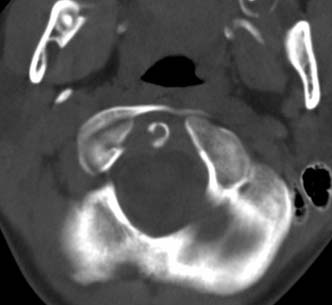

标题: PED0678:男,10岁,寰枢椎平扫。

患者在校与同龄孩子打闹后(据家长说被拳击中颈部)出现颈部不适30分钟后入院检查,来时脖子歪斜。请大家看看枢椎齿状突及寰枢关节有问题吗?(3mm层厚断层扫描)。